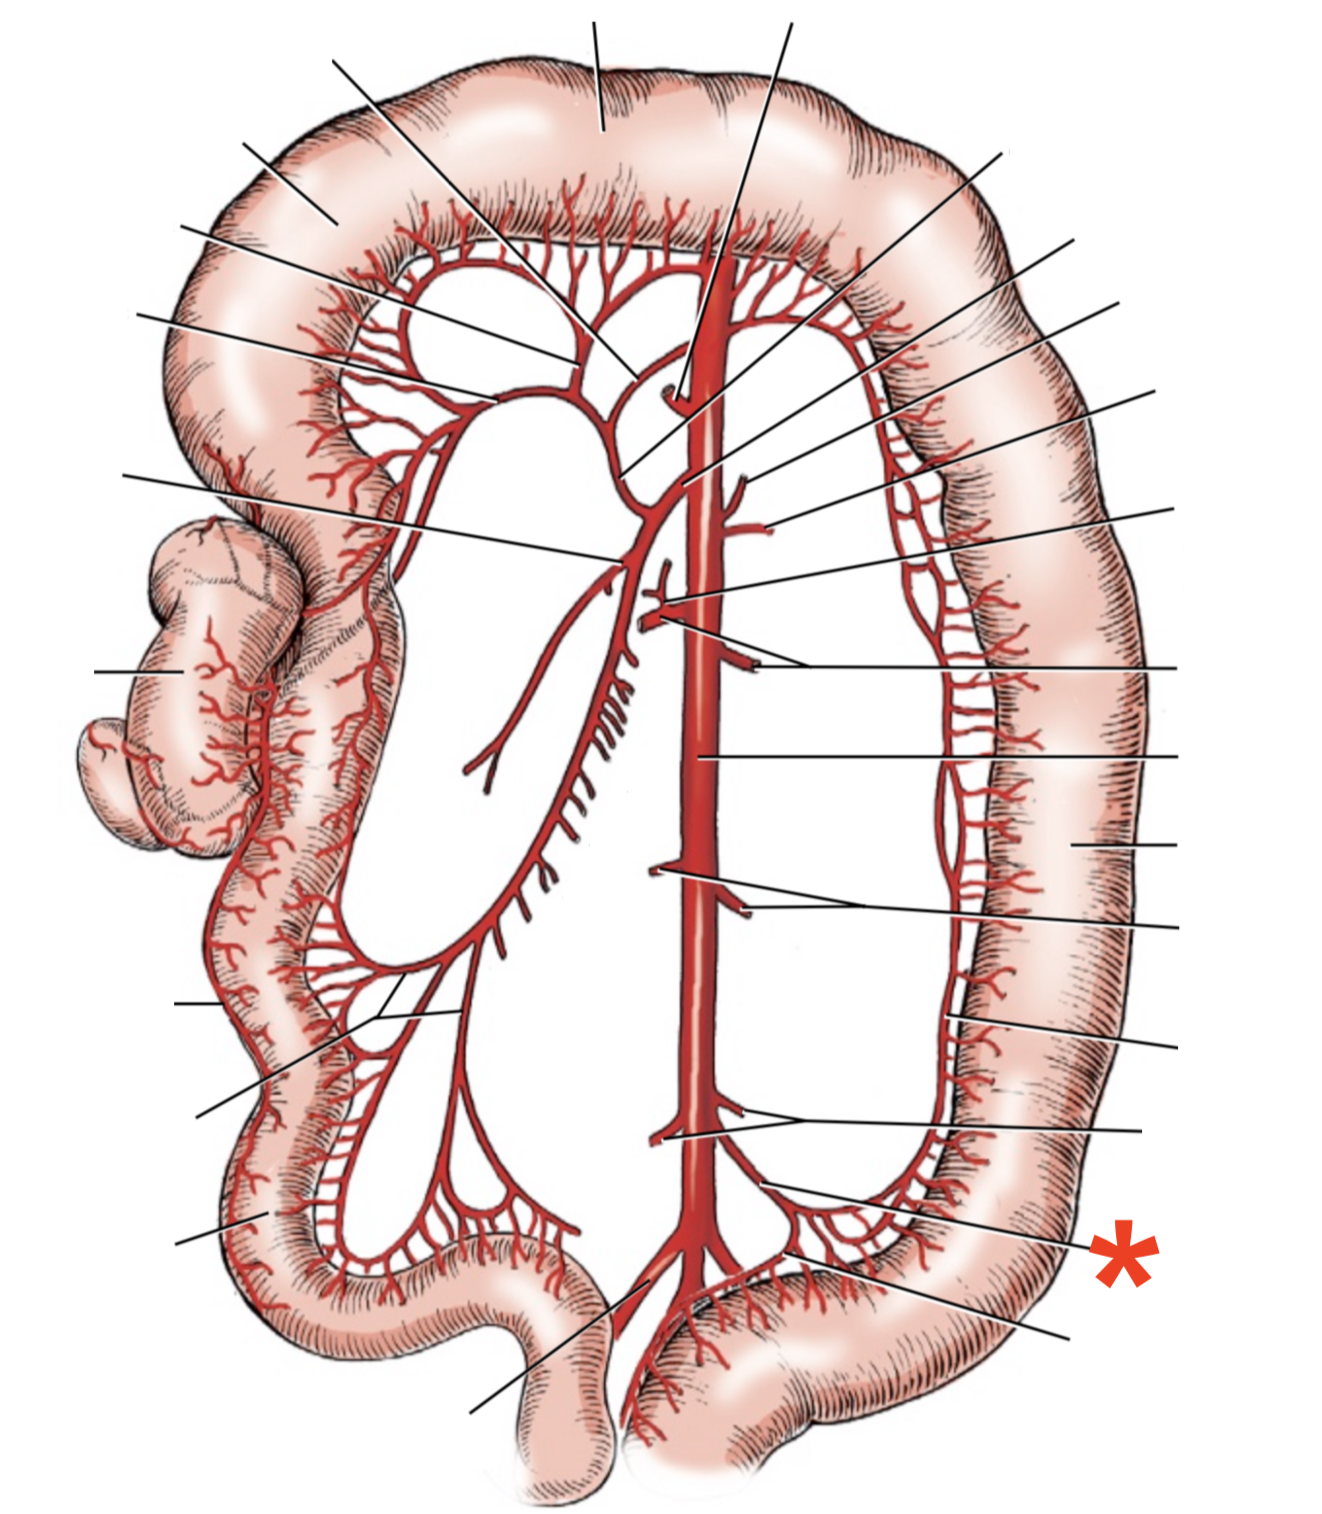

13

Q

A

A. mesenterica cranialis

15

Q

A

A. pancreaticoduodenalis caudalis

16

Q

A

Aa. jejunales

17

Q

A

A. ilei

- Anastomises with r. ileus mesenterialis a. iliocolica

18

Q

A

A. ileocolica

19

Q

A

A. colica dextra

20

Q

A

A. colica media

21

Q

A

A. mesenterica caudalis

22

Q

A

A. colica sinistra

23

Q

A

A. rectalis cranialis

List the branching of *a.* *mesenterica* *caudalis*

* *A. colica sinistra*

* *A. rectalis cranialis*

List the branches of *a.* *mesenterica* *cranialis*

* *A.* *pancreaticoduodenalis* *caudalis*

* *Aa. jejunalis*

* *A. ilei*

* Common trunk

* A. colica media

* A. colica dextra

* *A. ileocolica*

* *R. ilei mesenterialis*

* *A. cecalis*

* *R. colicus*